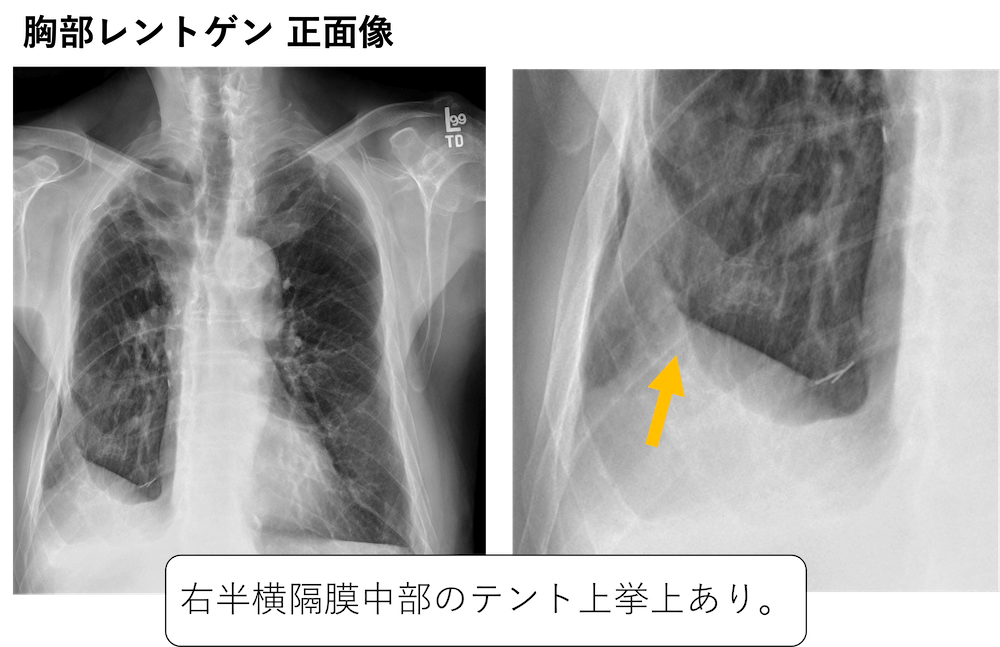

【同時梱包】歓迎ですが、当方の別IDとの同梱は保管場所が違うためできません。傍横隔膜隆起(juxtaphrenic peak sign)の胸部レントゲン、CT画像。当方の出品者IDにご注意ください。軽症の鈍的胸部外傷後に遅発性血胸を繰り返した横隔膜損傷の1例。